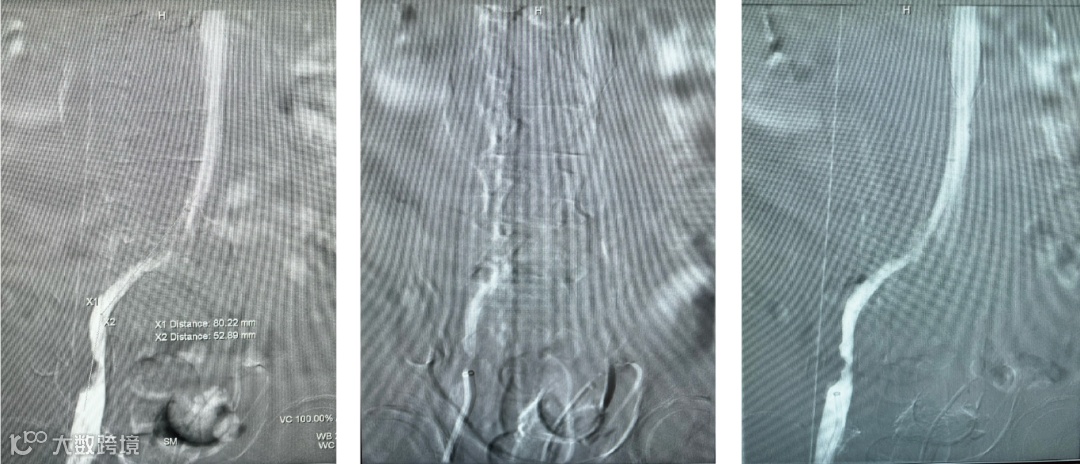

患者全程取俯卧位,左下肢常规消毒铺单,B超引导下穿刺左腘静脉,导入10F短鞘,经血管鞘造影,证实左腘股髂静脉血栓形成。鳅导丝配合单弯导管通过闭塞股静脉,造影证实导管位于下腔静脉。

导入10F天航外周血栓抽吸导管+天戟分离器于大腔导管行机械血栓清除

导入(10*60mm)球囊行髂静脉扩张

导入支架(14*100mm,)覆盖髂静脉狭窄处,再次造影见狭窄消失,股静脉回流通畅,原滤器内未见明显血栓形成,无造影剂外溢。拔管,穿刺点压迫止血,加压包扎。麻醉满意,术后患者安返病房。

最后造影见支架内血流通畅,侧枝消失